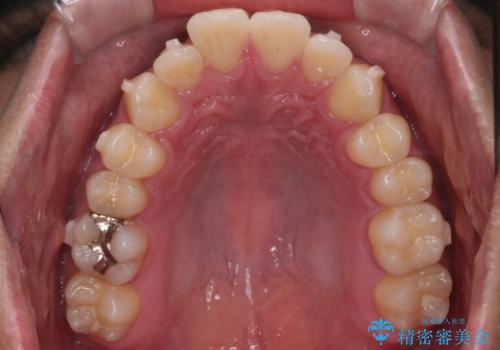

【インビザラインモニター】前歯が出ているのが気になる

- 上の前歯が出ているのが少し気になるとの事で来院されました。

インビザライン希望のため、IPR(歯と歯の間を削る処置)を行うことで、前歯の位置とがたつき整える治療計画を立てました。

患者様よりシュミレーション通りに歯が動くか心配との事だったので

出来るだけ計画通りに歯を動かすために、マウスピース1枚あたりの使用時間を長めに使っていただきました。

そのため、多少治療期間が延びましたが、リファイメント(マウスピースの再発注)なしで終了することができました。